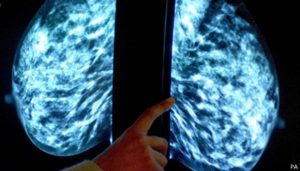

Un ensayo clínico internacional de fase 3 ha demostrado que la administración de un anticuerpo conjugado, un fármaco de última generación que transporta la quimioterapia de forma dirigida hasta la célula cancerígena, mejora los resultados en pacientes con cáncer de mama de alto riesgo en sus estadios más precoces.

El equipo investigador llevó a cabo un ensayo en fase III, la última etapa antes de la posible aprobación por las agencias reguladoras, para evaluar la eficacia del trastuzumab deruxtecan (T-DXd) administrado antes de la cirugía. Este anticuerpo conjugado funciona como un sistema de direccionamiento preciso: un anticuerpo se une específicamente a receptores presentes solo en las células cancerígenas y libera directamente el medicamento de quimioterapia, minimizando así el daño a las células sanas.

En el estudio participaron 641 pacientes con cáncer de mama HER2+ en estadios tempranos que no habían recibido tratamiento previo. La mitad de las pacientes fueron tratadas con el anticuerpo conjugado T-DXd, seguido del tratamiento habitual con paclitaxel, trastuzumab y pertuzumab (THP). La otra mitad recibió el tratamiento estándar con quimioterapia basada en antraciclinas, seguida de la misma triple combinación THP.

Los resultados fueron significativos: la tasa de respuesta patológica completa, que se alcanza cuando no queda ninguna célula cancerígena tras el tratamiento, fue del 67.3% en el grupo que recibió la combinación experimental. Esta cifra supera claramente el 56.3% observado en el grupo de tratamiento estándar.